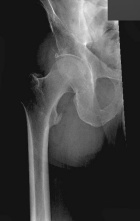

D.R. - 65 year old male, c/o worsening right hip/buttock pain for six months. Pain is constant, worse with activity. Tylenol helps a bit. No F/C or constitutional sx.

PMH: Crohn's disease, nephrolithiasis, prostate infection, gallstones